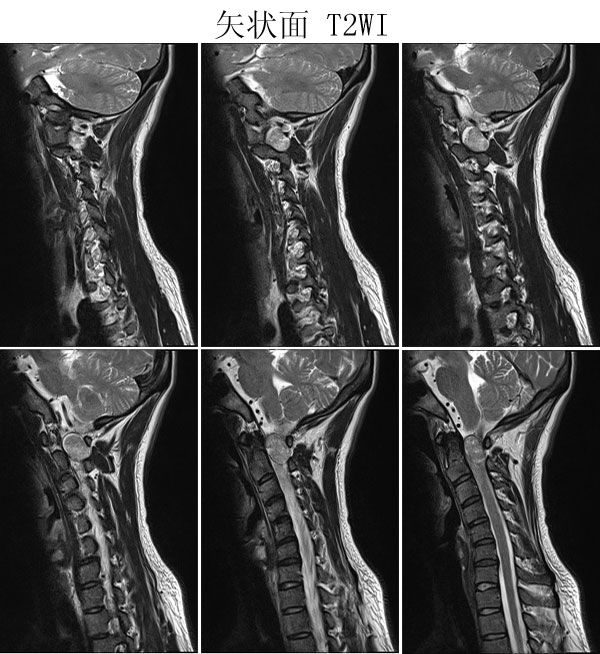

本病例来自广东同江医院

病史:女,27岁,洗头按摩时扭颈导致昏迷,检查发现颈椎占位

手术病理:

神经鞘瘤